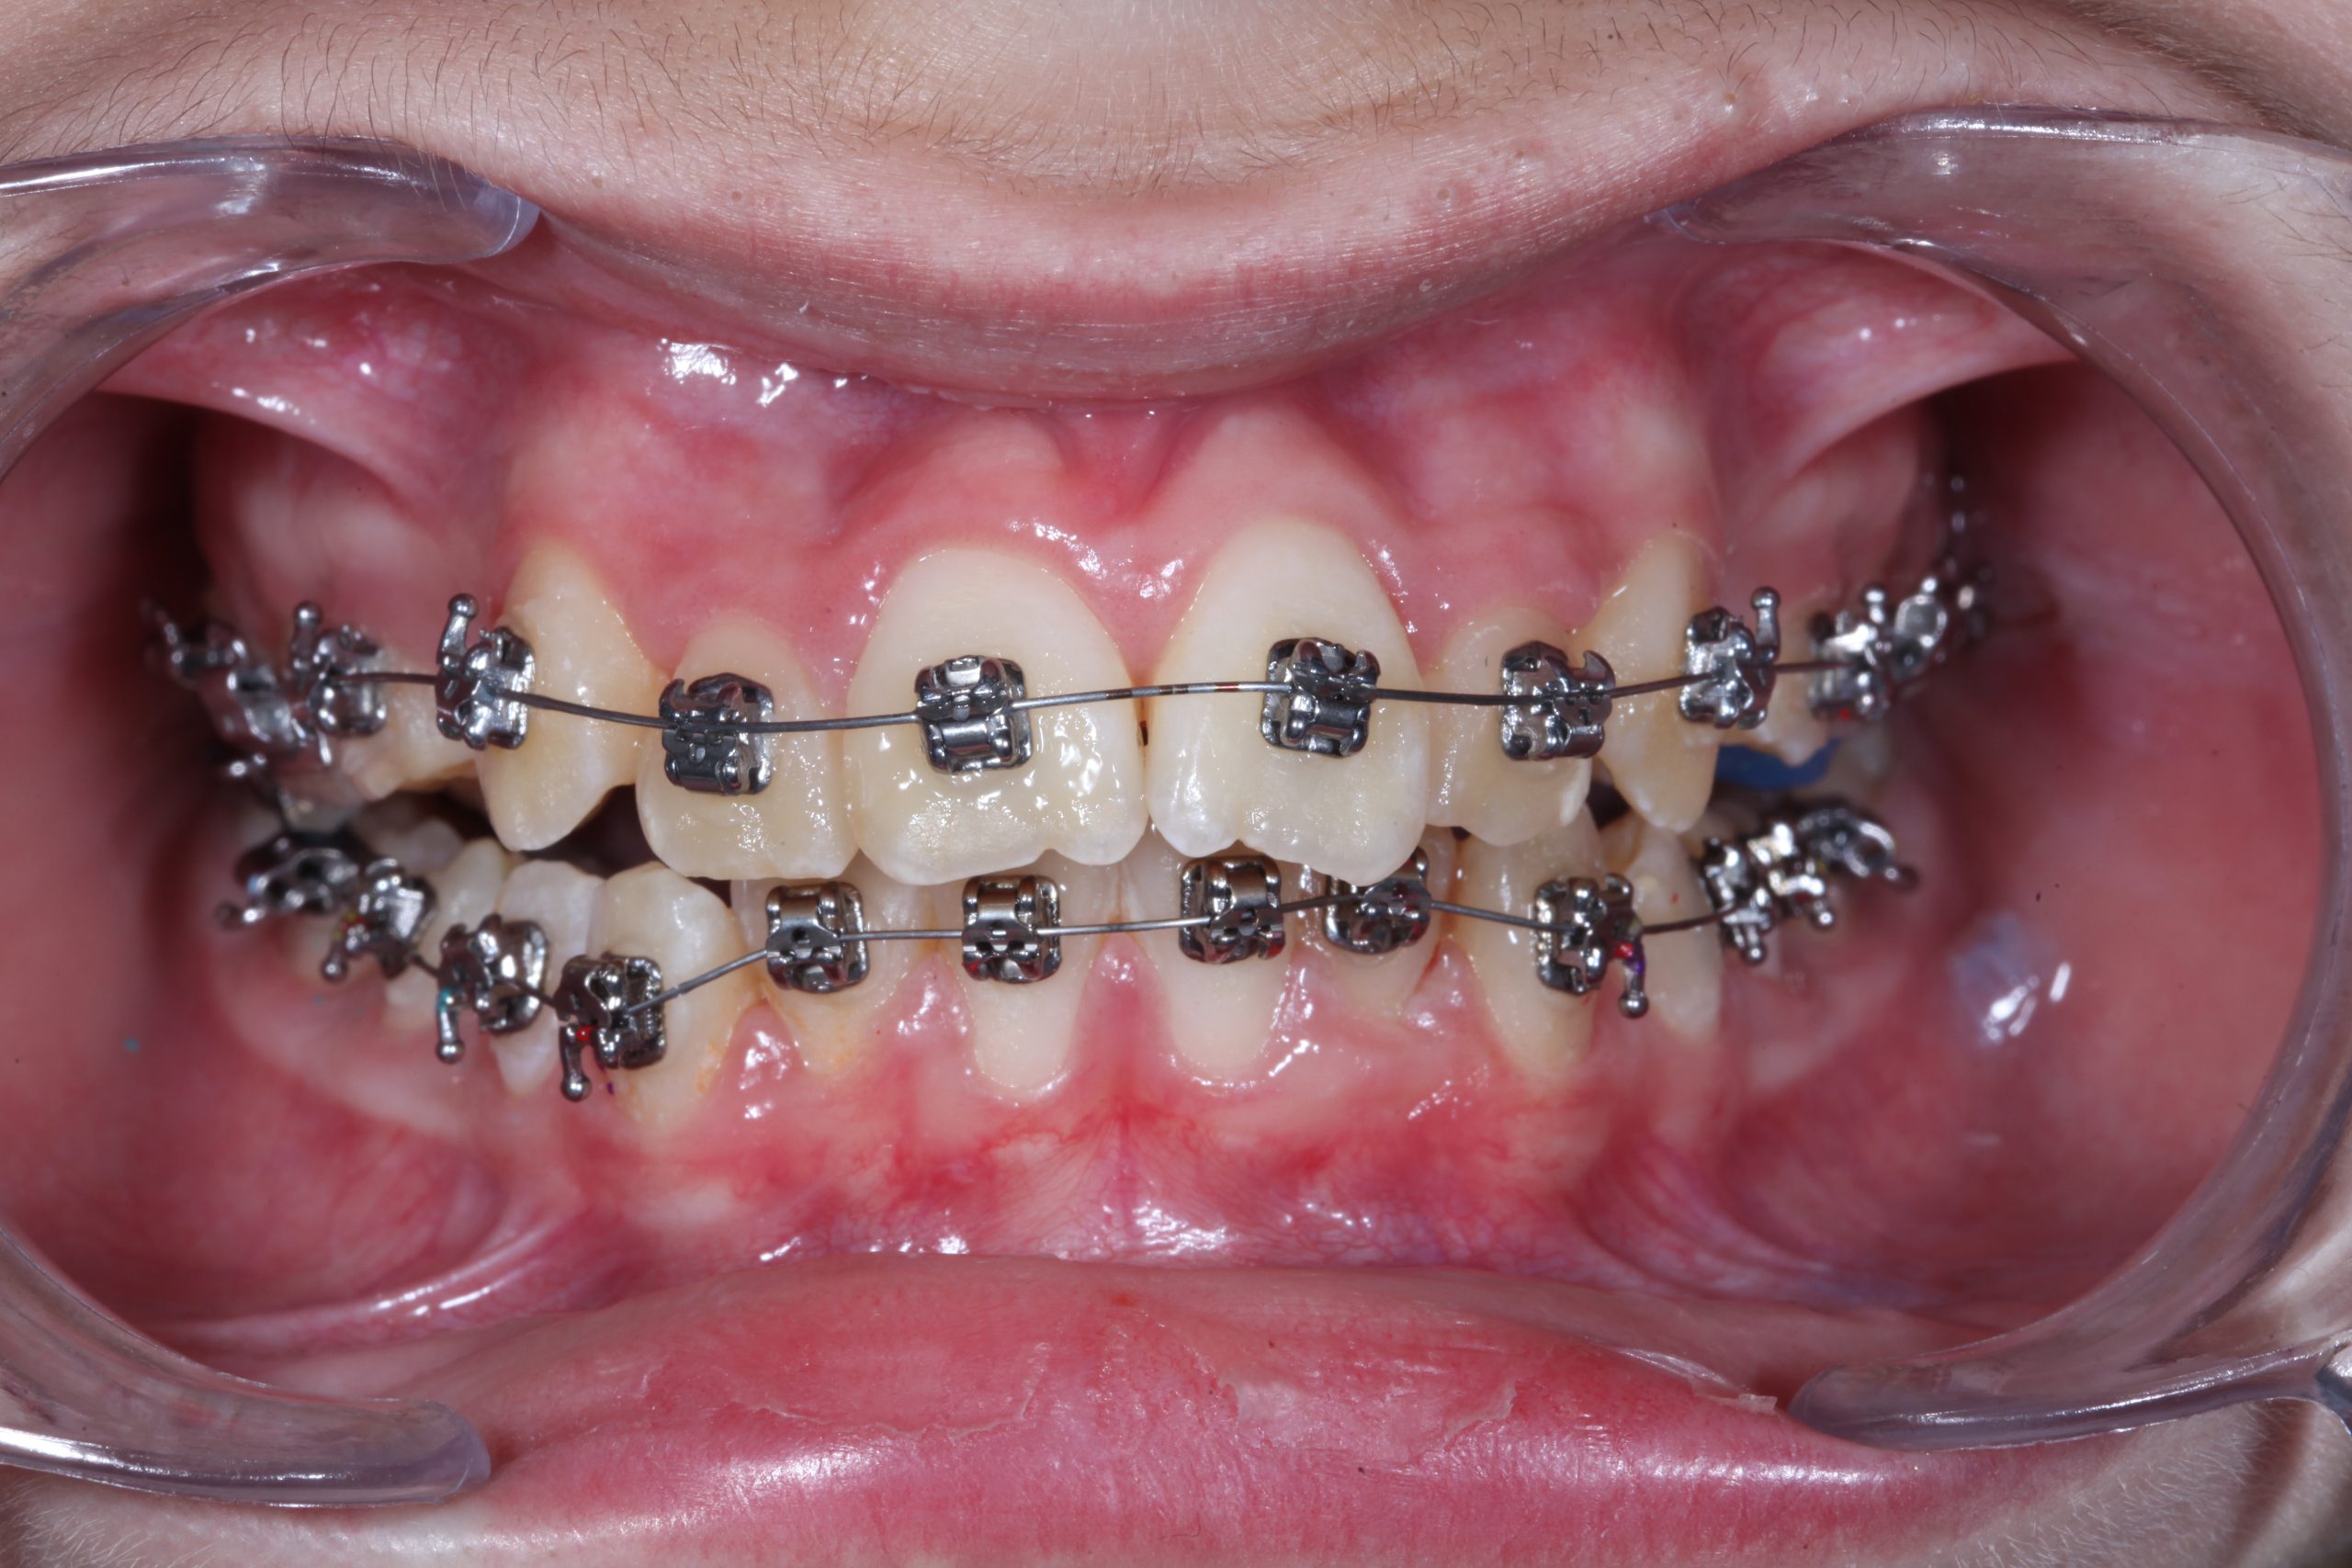

Metal-Seramik (Şeffaf) Braketler

Sabit ortodontik tedavilerde en sık kullandığımız yöntem metal braketlerle yapılan tedavilerdir. Dişlerin ön yüzeyinden uygulanan bu braketler ve teller dişlerin düzeltimini gerçekleştirir.